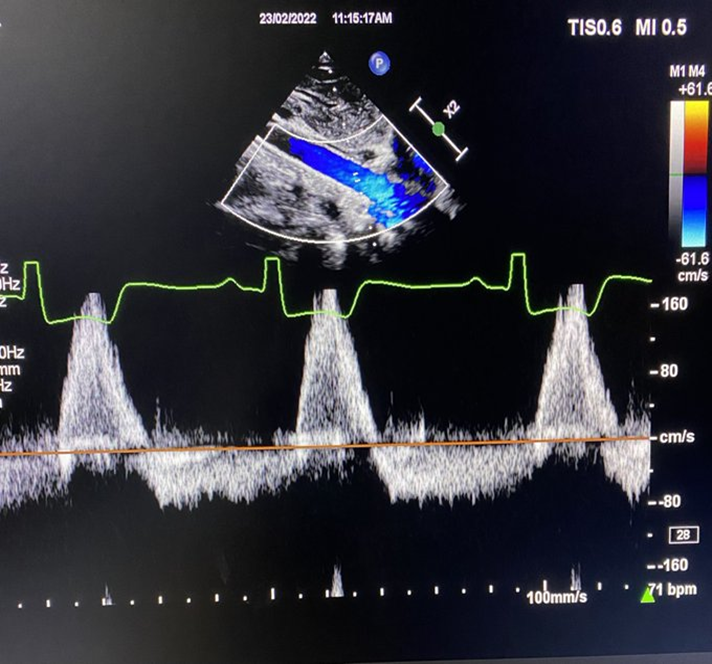

what do you look for with pulmonary vein systolic flow reversal?

look for reversal of S wave